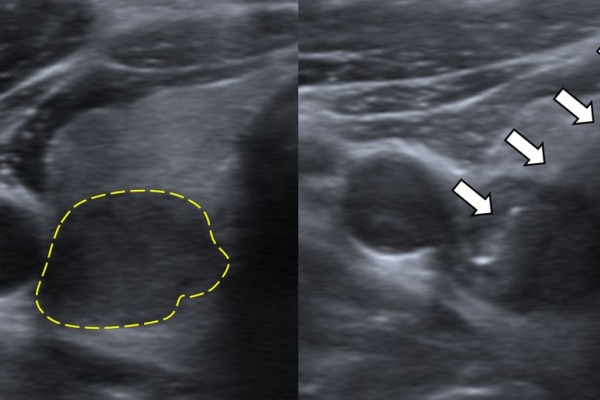

Η διαδερμική βιοψία είναι μία ελάχιστα επεμβατική μέθοδος λήψης υλικού από τον όγκο για κυτταρολογική και ιστολογική εξέταση, από εστιακές αλλοιώσεις του ήπατος, πνεύμονα, νεφρού κλπ. Συστήνεται από τον κλινικό ιατρό ανάλογα με το είδος και το μέγεθος της βλάβης και πραγματοποιείται με ασφάλεια από επεμβατικό ακτινολόγο με την καθοδήγηση αξονικού τομογράφου ή υπερήχων. Στη σύγχρονη ογκολογική θεραπεία όπου γίνεται προσπάθεια καταπολέμησης του καρκίνου σε μοριακό επίπεδο κρίνεται αναγκαία η ακριβής ιστολογική ταυτοποίηση του όγκου ώστε να εφαρμοσθεί εξατομικευμένη θεραπεία για το βέλτιστο αποτέλεσμα. Οι κατευθυνόμενες βιοψίες στοχευουν στο να παρέχουν στον κλινικό ογκολόγο το απαραίτο ιστοπαθολογικό υλικό που θα του επιτρέψει να εφαρμόσει την κατάλληλη θεραπεία για τον ογκολογικό ασθενή.